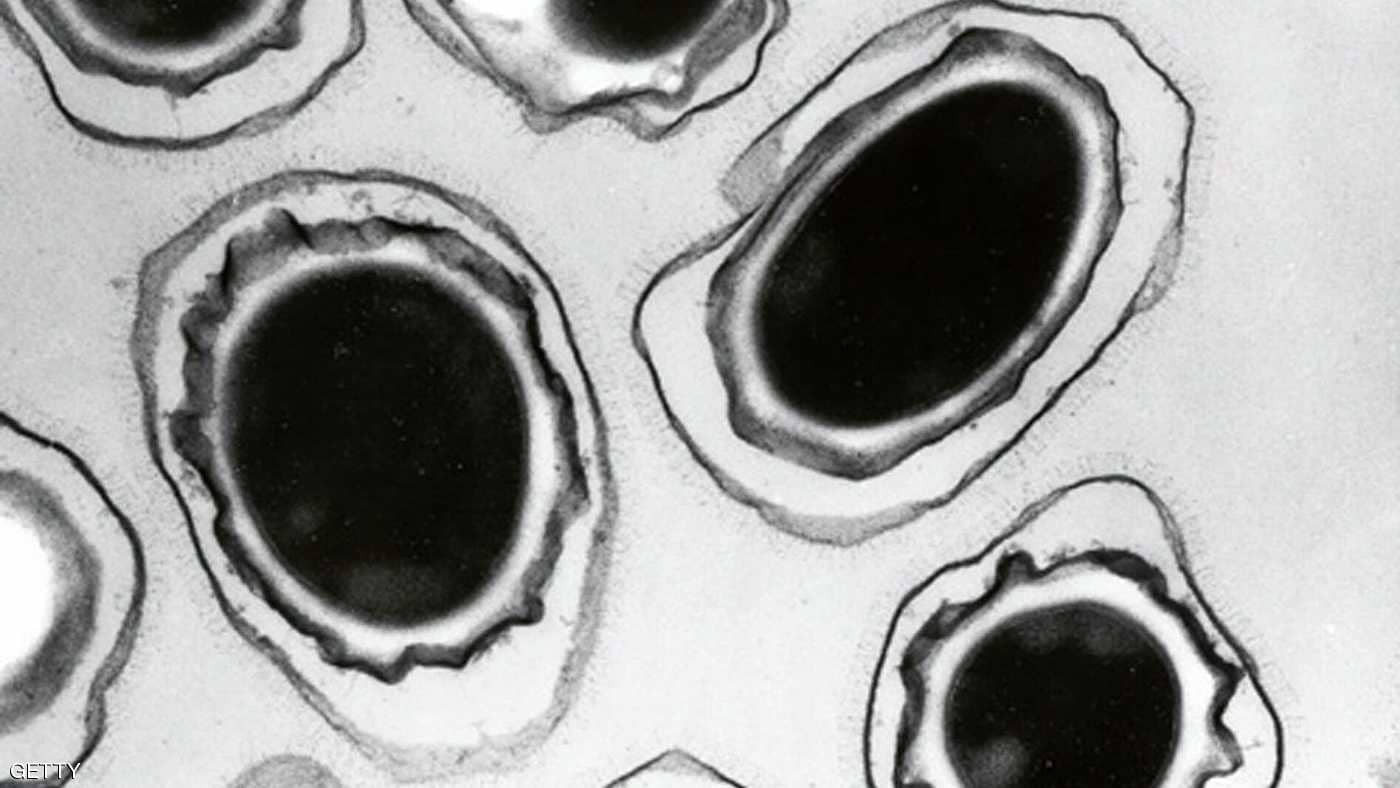

وتتطور المقاومة للدواء بفعل إساءة استخدام المضادات الحيوية وغيرها من الأدوية المضادة للميكروبات، أو الإفراط في استخدامها، الأمر الذي يشجع البكتيريا على التطور من أجل البقاء بإيجاد طرق جديدة للتغلب على الدواء.

وخلص التقرير إلى أن مقاومة بكتيريا تعرف باسم "كامبيلوباكتر"، ويمكن أن تصيب الإنسان بالتسمم الغذائي، لأحد المضادات الحيوية شديدة في بعض الدول، لدرجة أن هذه الأدوية لم تعد فعالة في علاج الحالات الخطيرة.

وأضاف التقرير أن معظم الدول قالت إن مقاومة بكتيريا "سالمونيلا" التي تصيب البشر للمضاد الحيوي "فلوروكينولونيز" تزداد، كما أن مقاومة 3 أو أكثر من مضادات الميكروبات شديدة في بكتيريا "سالمونيلا" التي تصيب البشر والحيوانات.